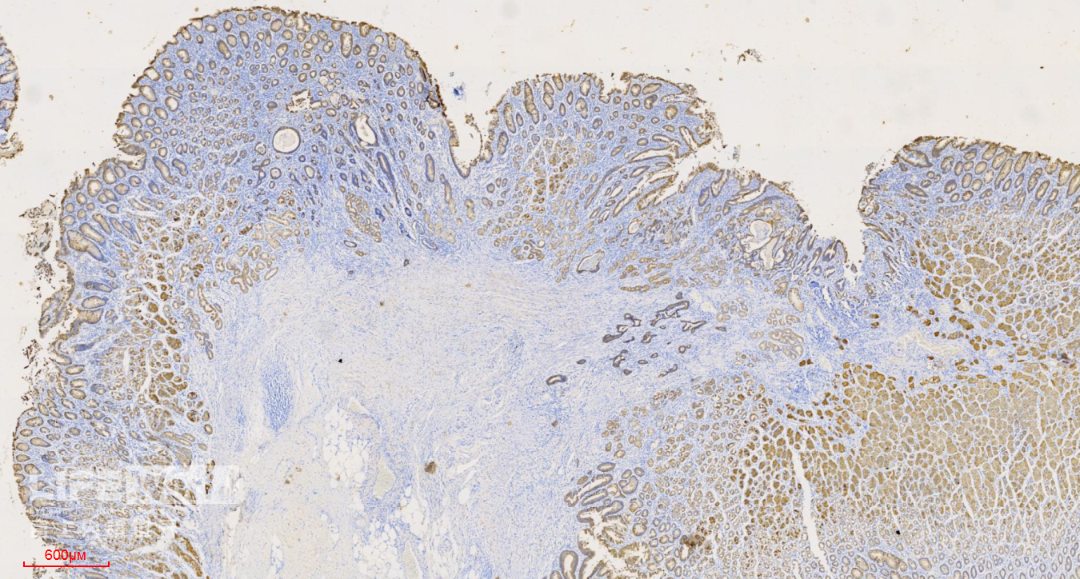

HE染色:2号切片示中分化腺癌,6号切片示高级别上皮内瘤变,局灶癌变。

这是2号切片,病变位于一条皱襞顶端。

病变处(红圈内)可见不规则的腺管状结构,部分呈筛网状。图中可以看出,病灶间可见相对正常的胃底腺结构。图片中最深的病灶已经侵及粘膜肌层。

CK-pan染色显示肿瘤细胞为上皮细胞,呈不规则腺管状排列,提示为中分化腺癌。

SMA染色:粘膜肌层完整,肿瘤细胞侵及粘膜肌层,但未突破。